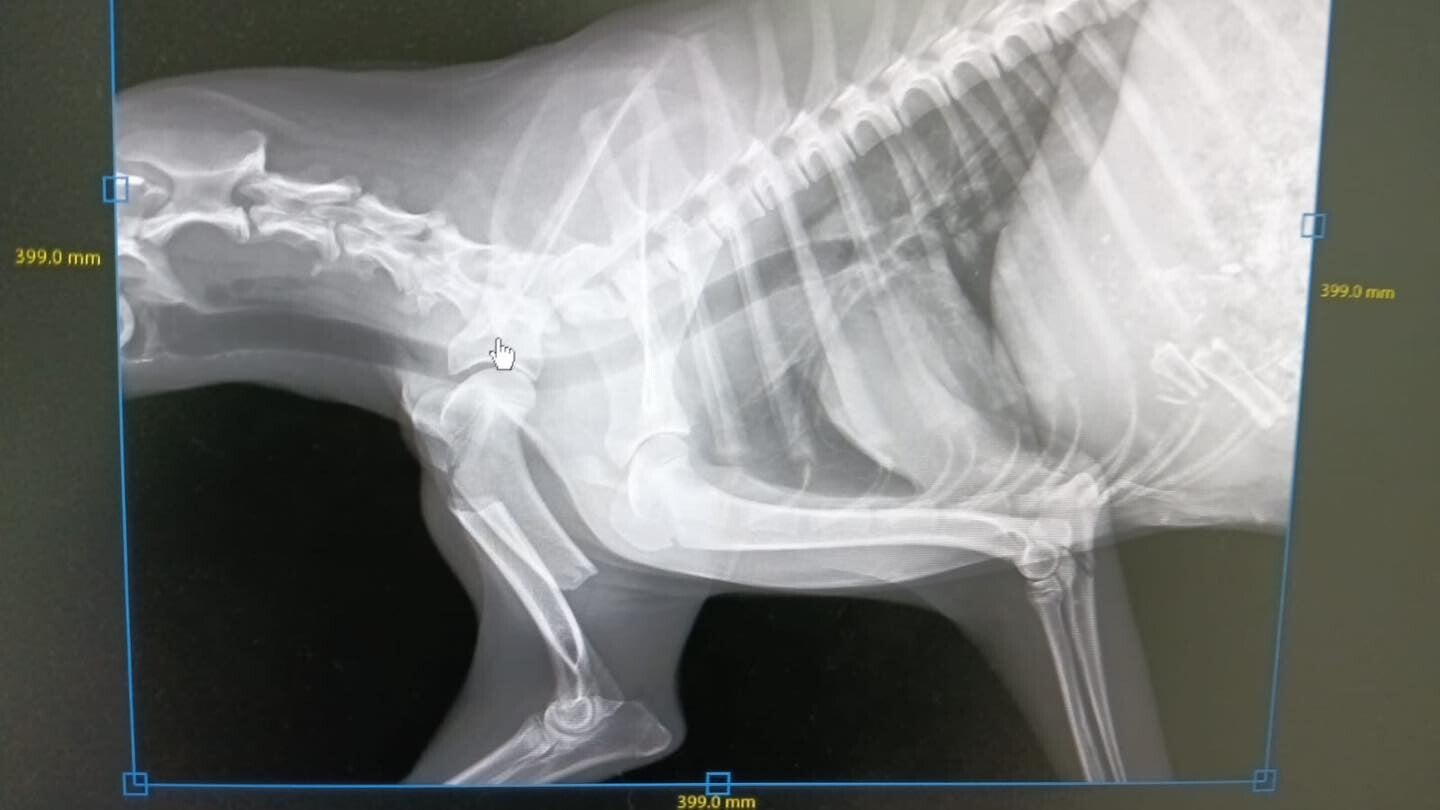

Dit is  Flavia, ze is ongeveer een jaar oud en op brute wijze overreden. Ze heeft twee gebroken benen,  een gebroken opperarmbeen op één van de voorste ledematen, en één van de achter ledematen. de kop van de dijbeen en de heup zijn gebroken en dan heeft ze ook nog een scheur in de maag.